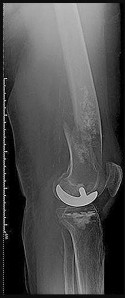

Question 14:

A 70-year-old female undergoes a primary posterior-stabilized total knee arthroplasty. Intraoperatively, the surgeon realizes that the knee is well-balanced in extension but unacceptably tight in flexion. Which of the following technical errors most frequently causes an isolated tight flexion gap?

Options:

- Excessive distal femoral resection

- Oversizing the femoral component in the anteroposterior (AP) dimension

- Undersizing the femoral component in the anteroposterior (AP) dimension

- Increasing the posterior slope of the tibial cut

- Recessing the joint line (patella alta)

Correct Answer: Oversizing the femoral component in the anteroposterior (AP) dimension

Explanation:

The flexion gap in TKA is dictated primarily by the size of the posterior femoral condyles and the AP dimension of the femoral component. Oversizing the femoral component in the AP dimension (and specifically adding posterior offset) stuffs the posterior joint space, leading to a tight flexion gap. Excessive distal femoral resection affects the extension gap (making it loose). Increasing the posterior tibial slope would actually increase (loosen) the flexion gap.